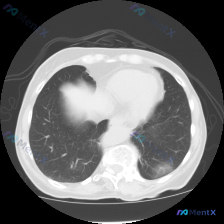

看到一个胸部CT肺窗的病例资料,整理了一下分析思路,和大家分享讨论。 先看一下影像的基本信息: - 图像质量清晰,肺窗显示良好,无明显伪影 - 解剖定位在主动脉弓或气管隆突上方,可见双侧肺门血管和气管影 - 左肺上叶可见多发小结节,圆形或类圆形,边缘相对锐利,部分密度较高,主要分布在支气管血管束周围...

整理了一个胸部CT病例资料,给大家分享下分析思路。 【病例信息】 - 影像层面:胸部上段CT肺窗,大致主动脉弓水平附近 - 异常表现:双肺上叶散在的微小实性及亚实性结节影 - 左肺上叶:数个散在微小结节,部分边缘模糊,伴有轻微磨玻璃密度改变,主要在左肺上叶前段 - 右肺上叶:散在点状高密度影,边缘相...

看到一份胸部CT肺窗的影像资料,整理了一下分析思路: 首先看基本情况:双肺透亮度对称,肺纹理走行自然,未见实变、肺不张或严重肺气肿。肺门血管正常,气管和主支气管开口显示良好,胸膜光滑,纵隔居中,心脏大小形态正常。 重点异常是左肺下叶靠近后胸膜处的一个小结节,直径估计数毫米,密度呈实性,边界相对清晰,...

看到一张胸部CT肺窗横断面图像,整理了一下分析思路,和大家讨论。 病例资料: 患者的详细病史和其他检查结果未提供,仅提供了这张CT肺窗图像。 影像观察: 1. 扫描层面位于心室水平上方、肺门区域(主肺动脉分叉附近),可见升主动脉、降主动脉、主肺动脉及其分支、气管周围血管结构。 2. 双肺透亮度对称正...